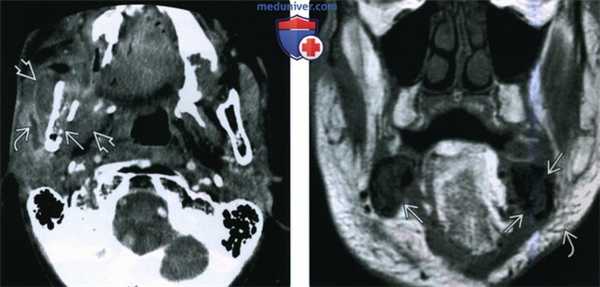

(Слева) При аксиальной КТ в коаном окне у пациента, получавшего лучевую терапию по поводу ПКР носовой перегородки, определяются литические изменения в передних отделах верхней челюсти, визуализируется фрагмент разрушенной кости.

(Справа) При аксиальной КТ в костном окне у другого пациента определяются изменения, обусловленные резекционным вмешательством на небе справа, видны также очаги литического и склеротического характера в верхней челюсти слева, которая также была подвергнута облучению. Верхняя челюсть относительно устойчива к лучевому воздействию и мало подвержена ОРН. Лучевые признаки ОРН верхней челюсти идентичны таковым для нижней челюсти, других костей лицевого скелета и основания черепа.

(Слева) При аксиальной КТ с КУ определяются признаки остеорадионекроза нижней челюсти справа, осложненного инфекцией жевательного пространства. Определяется дефект кортикальной пластинки, а также выраженный отек околоушной железы и жевательных мышц. Визуализируется расширенный проток околоушной железы, заполненный воспалительным дебрисом.

(Справа) При корональной МРТ Т1ВИ определяется диффузное замещение сигнала, типичного для жира, в костном мозге. Визуализируются также множеавенные дефекты кортикальной пластинки. Уплотнение и отек подкожной жировой ткани также часто обнаруживаются при ОРН нижней челюсти.